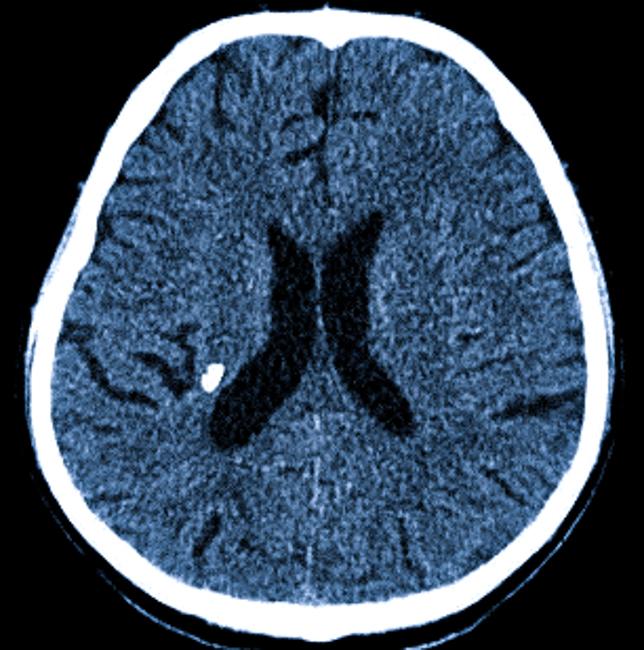

Компьютерная томография. Обнаружить болезнь Фара по результатам КТ проще, так как данный метод позволяет точно определить размер и местоположение патологических образований.

Наиболее информативным и достоверным способом выявления болезни Фара является компьютерная томография. Этот метод позволяет детально рассмотреть каждое место обызвествления и его размер.

Компьютерная томография демонстрирует гиперденсивные очаги (локусы повышенной плотности), связанные с симметричным двусторонним отложением кальция в:

- в базальных ганглиях;

- в зубчатых ядрах мозжечка;

- в таламусе;

- в субкортикальном белом веществе;

- в коре больших полушарий и других областях головного мозга;

- в сосудах — мелких артериях и артериолах.

Широкое обызвествление наблюдается крайне редко. Интенсивность кальцинированных участков на снимках отражает уровень содержания кальция. Считается, что для появления симптомов общая площадь кальцинированных областей должна составлять не менее 3,9 см³.

Кальцинаты на КТ мозга

Единичные кальцинаты являются довольно частыми находками на КТ.